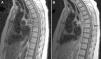

Case presentationA 68-year-old female was referred by her primary physician to the ER for evaluation and management of severe pain in her back along the rib cage, which radiated towards the anterior abdominal wall. She reported that the pain was 10/10 in intensity, sharp in quality, continuous, and increased with movements. She also complained of mild fever with lethargy. She denied weakness of the limbs and fecal or urinary incontinences. The patient had past medical history of hypertension and gastroesophageal reflux disease (GERD). She had undergone esophagogastroduodensoscopy (EGD) two weeks prior, which was positive for submucosal cyst. She had diffuse tenderness over her back, which was more significant over the lower thoracic vertebrae. Laboratory data showed a WBC count of 18,000, with neutrophilic predominance of 91.4%. Erythrocyte sedimentation rate (ESR) and C-reactive protein (CRP) level were 120mm/hour and 207.5mg/L respectively. Magnetic resonance imaging (MRI) of the thoracic spine (Fig. 1A and B) was performed, which revealed an abscess on the posterior aspect of the spinal cord displacing the spinal cord anteriorly at the level of T5 and T6. Another abscess anterior to the spinal cord, which was displacing the spinal cord posteriorly at the level of T6 and T7 extending to T8, was also observed. There was signal abnormality of the bodies of T6 and T7 vertebrae consistent with osteomyelitis. The patient was started empirically on intravenous vancomycin and doripenem, with pending blood cultures. Two blood cultures isolated from the patient one hour apart at the time of admission grew Gram-negative rods positive for anaerobic bacteria, P. oralis. The body fluid aspirated from the abscess was also positive for P. oralis. The API® 20A anaerobic system (bioMérieux Inc.) was used in identification of bacteria. Antibiotics were changed to ampicillin-sulbactam and metronidazole after the availability of culture reports. The patient was later transferred to a skilled nursing facility with a long-term intravenous access, and later responded well to the treatment after antibiotic therapy for eight weeks.